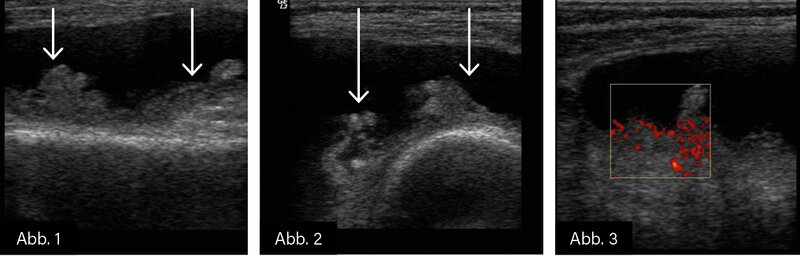

BILDGEBUNG: Gelenksonografie (s. o.)

DIAGNOSE: Proliferative Synovialitis bei seropositiver RA

Die Gelenksonografie hat sich als ein wichtiges bildgebendes Verfahren zur Diagnostik und Verlaufsbeurteilung der proliferativen Synovialitis bei rheumatoider Arthritis (RA) etabliert. Sie ermöglicht eine frühzeitige Erkennung von entzündlichen Veränderungen der Synovialmembran, die für die RA charakteristisch

sind.

- PD-Sonografie (PDUS): Diese Technik ermöglicht die Darstellung der synovialen Durchblutung als Zeichen aktiver Entzündung. Eine verstärkte Vaskularisierung korreliert mit einer höheren Krankheitsaktivität und einem erhöhten Risiko für strukturelle Gelenkschäden.